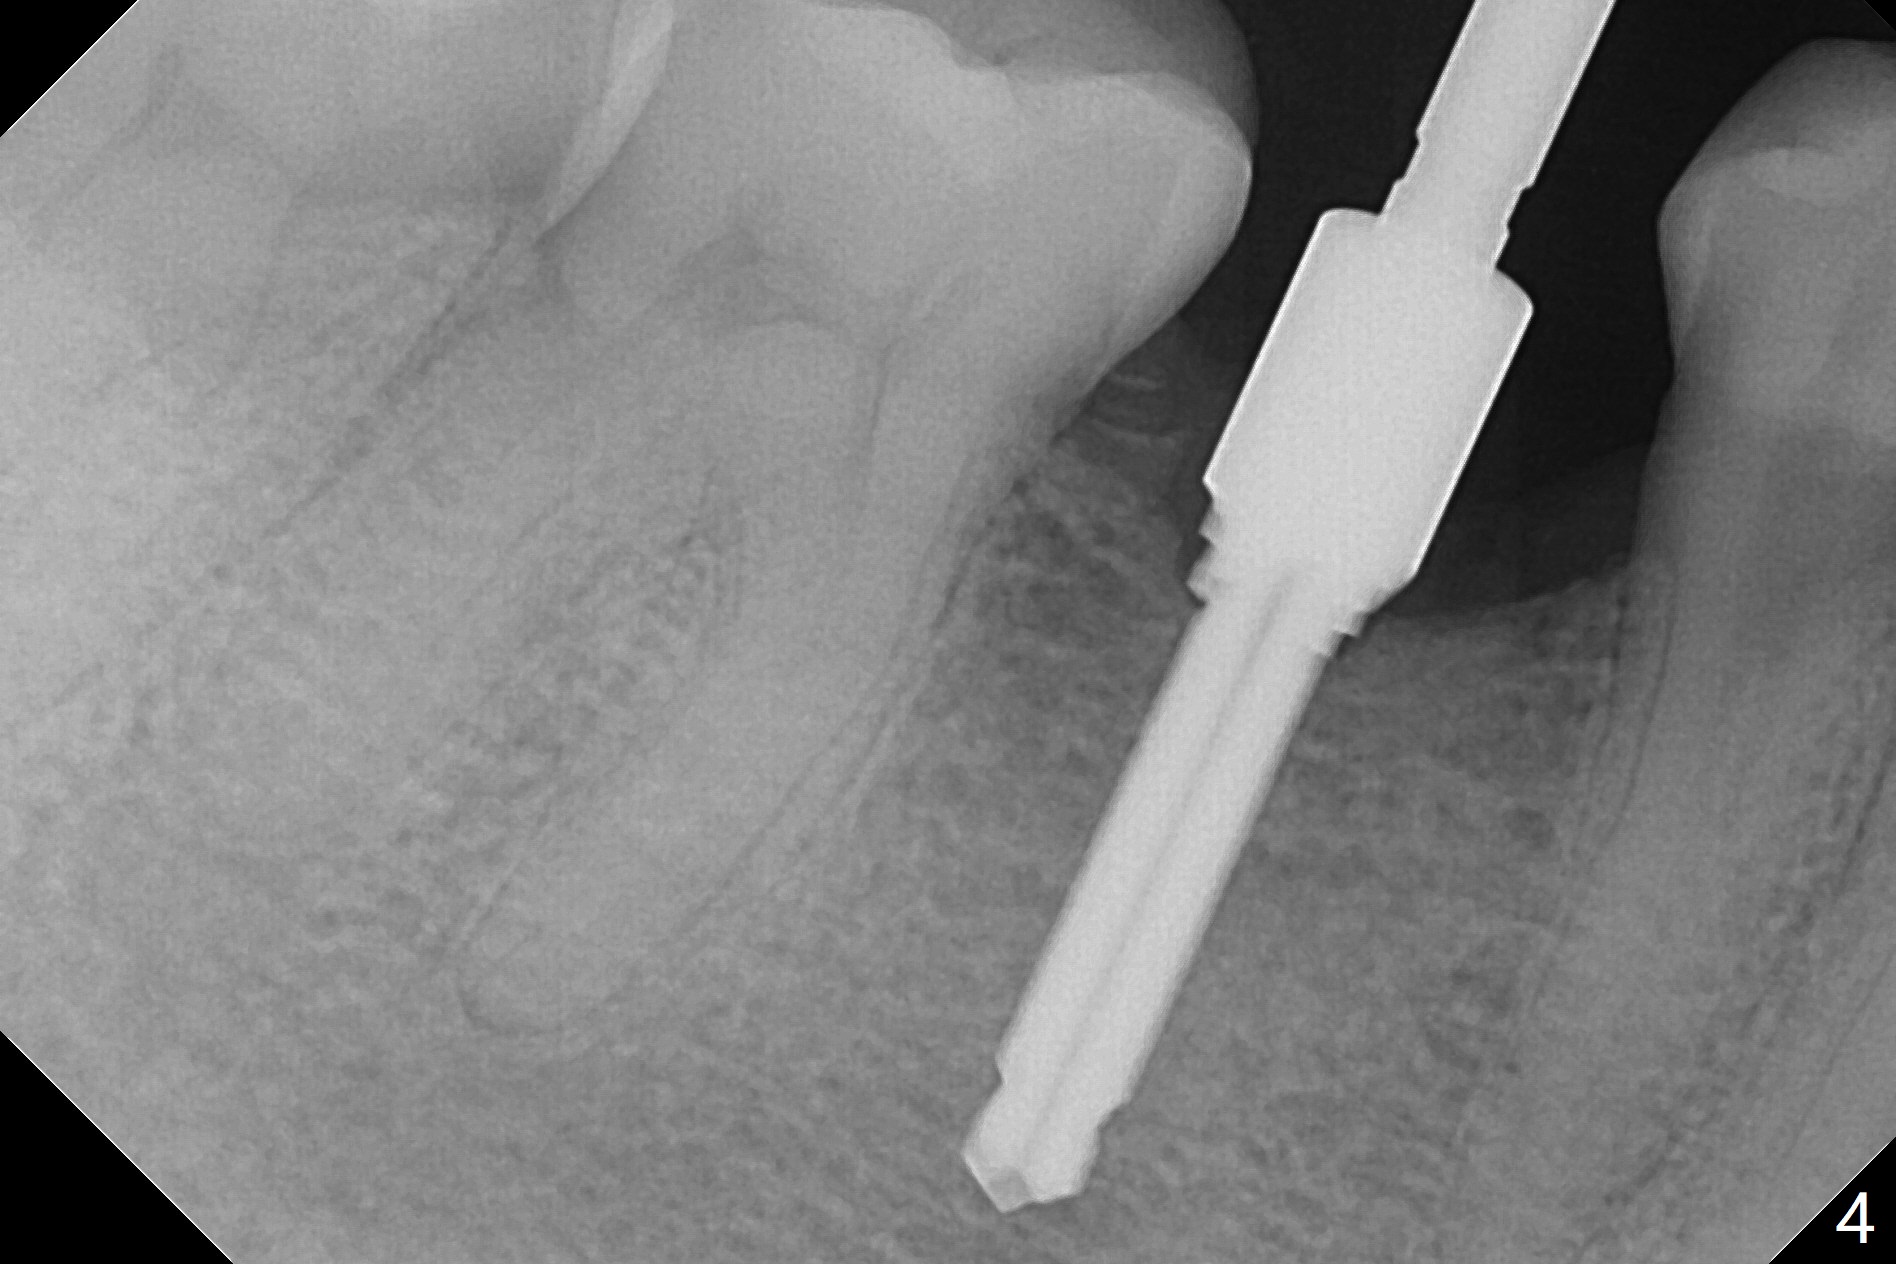

The base of the edentulous ridge at #29 looks wide (Fig.1), but the most coronal portion is the thin soft tissue (Fig.2). It appears that there has been bone resorption since extraction. The initial osteotomy depth is 11.5 mm (Fig.3). Since the Mental Loop seems to be nearby, the depth of subsequent osteotomy (3 mm) remains the same (Fig.4). Although the final depth of osteotomy is 13 mm, the implant placed is short (3.8x11.5 mm, Fig.5,6), as compared to the immediate implant (3.8x18 mm) at the contralateral side (#20). There is mild bone resorption mesially 4 months postop (Fig.7). The crown is loose (poor osteotomy position, guide necessity) 7 months post cementation immediately prior to 18 cementation, although there is no gross bone losss 1 year 7 months post cementation (Fig.8).